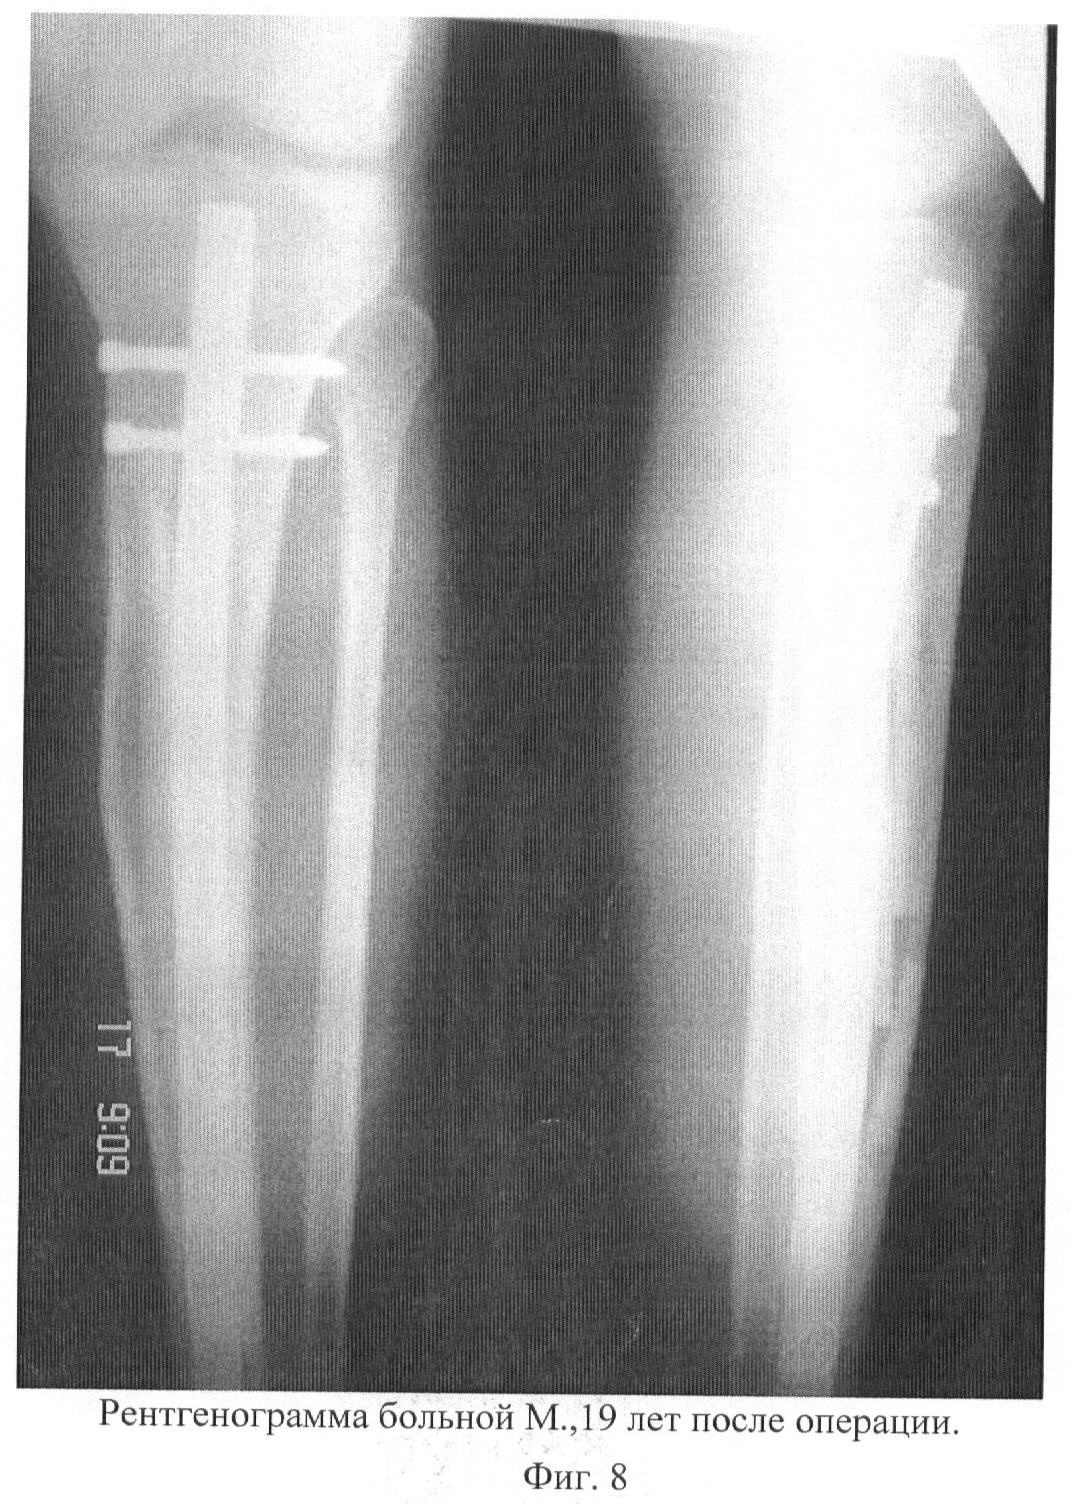

На клиническом разборе решено провести оперативное лечение: краевая резекция большеберцовой кости, интрамедуллярный блокирующий остеосинтез с костной пластикой дефекта аллоплантом. Решение провести блокирующий остеосинтез было вызвано тем, что имелась опасность перелома из-за потери механической прочности кости после ее краевой резекции, а длительная внешняя иммобилизация и длительная ходьба на костылях вела к тяжелым последствиям (контрактуры суставов, синдром Зудека и пр.). После соответствующей подготовки больная была прооперирована по вышеописанной методике (фиг.8).

С первых суток после операции разрешена полная нагрузка на оперированную конечность, начата лечебная физкультура, проводились перевязки, симптоматическое лечение. Неосложненный послеоперационный период. Послеоперационная рана зажила первичным натяжением. К моменту снятия швов полностью восстановлена функция конечности, исчезли боли. Больной разрешено давать полную нагрузку. Проведенный блокирующий интрамедулярный остеосинтез с костной пластикой аллоплантом позволил больной нести полную нагрузку на пораженную конечность и вести полноценный образ жизни, не боясь возникновения патологического перелома. Получен хороший функциональный результат и полная социальная и медицинская реабилитация.